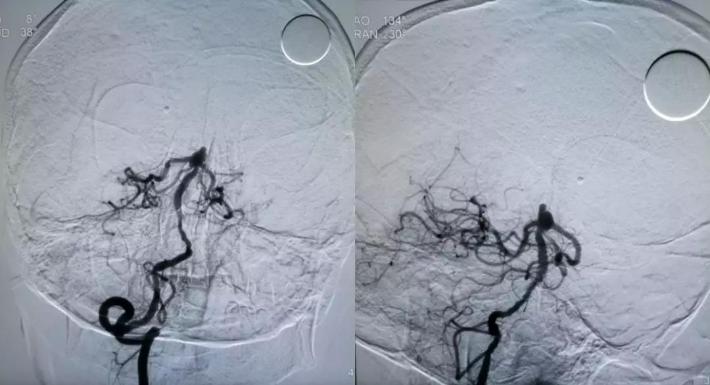

拟通过微导丝将支架微导管预置到右侧大脑后动脉,但微导丝支撑力不足,直接通过基底动脉至右侧大脑后动脉较困难,先在动脉瘤腔内部分填塞弹簧圈(4mm*10cm),以作支撑,再将微导丝带微导管置入右侧大脑后动脉,经微导管送入LEO支架(2.5*18mm)

采用支架半释放技术,LEO 2.5*18mm半释放,继续送入编框圈编框成篮,再依次填入填充圈

采用支架推挤技术,推挤支架,保护双侧大脑后动脉、右侧小脑上动脉,继续将动脉瘤填塞致密,完全打开支架